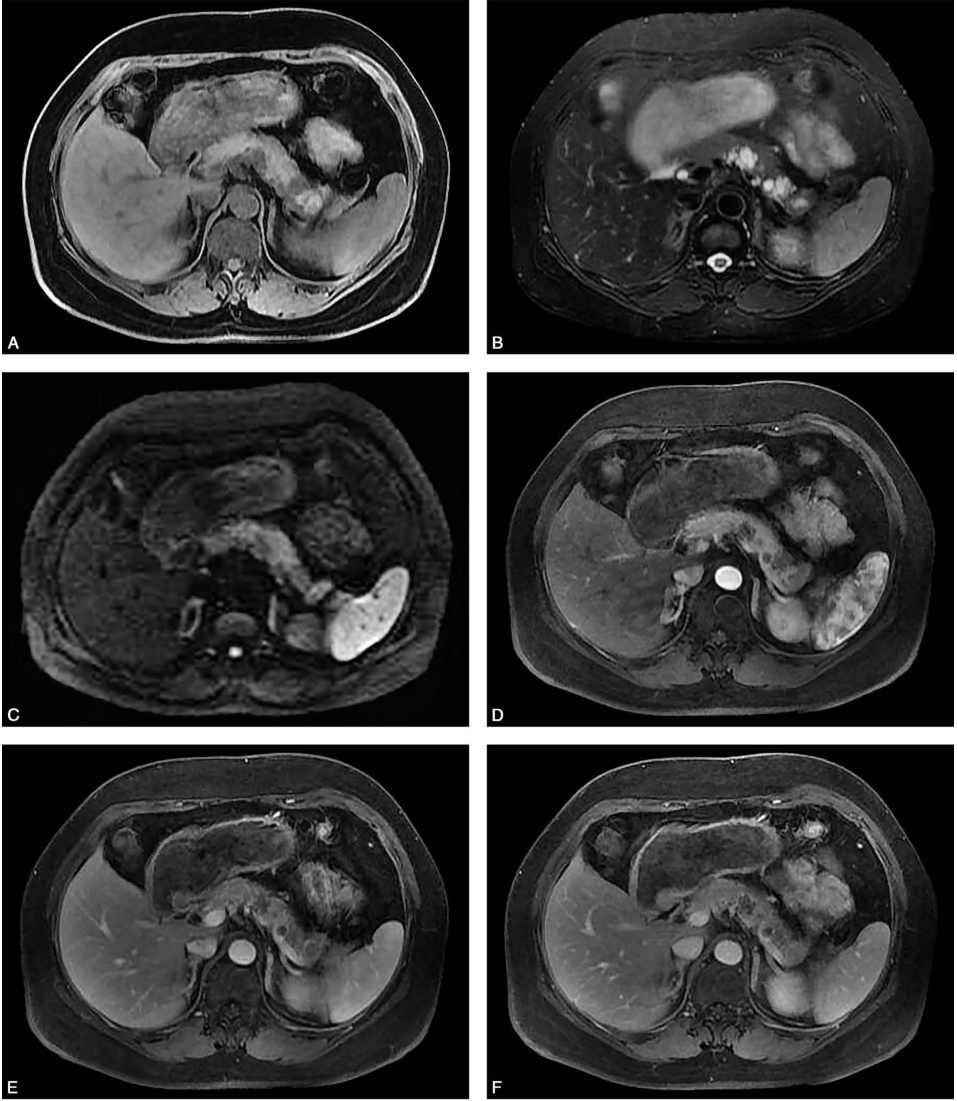

腹部MRI增强(图2)示胰体尾多发类圆形异常信号灶,T1WI呈低信号,T2WI呈高信号,DWI呈低信号,部分其内可见分隔影,增强扫描分隔可见强化,囊性成分未见强化。

图2 腹部增强MRI

A.T1WI;B.T2WI;C.DWI;D.动脉期;E.静脉期;F.平衡期。